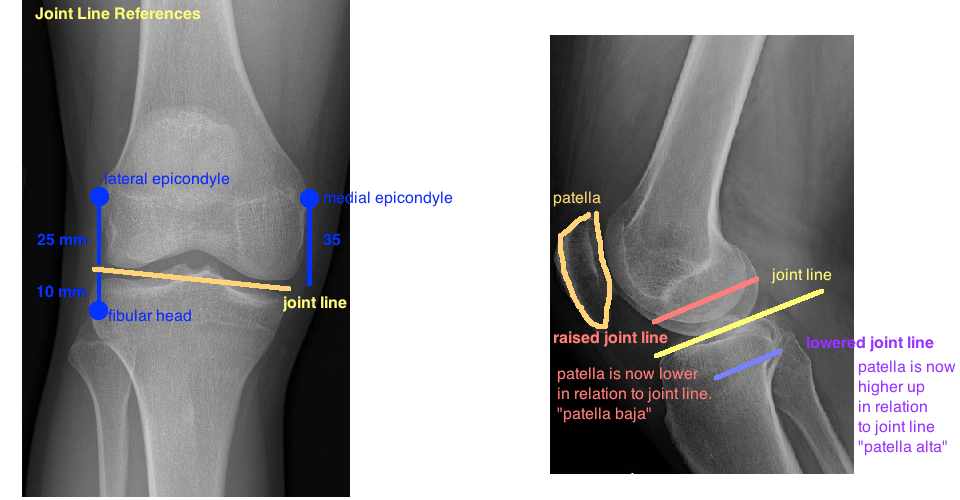

From dontforgetthebubbles.com

Knee Xrays Don't the Bubbles White Lines On Knees Evidence of chondrocalcinosis is the presence of a white line in the cavities at the ends bones. Learn how to assess your knee injury and when to see a doctor from. Swelling in the knee that comes on quickly and is hard to see is a sign of a serious injury, such as a torn acl. As cartilage is lost. White Lines On Knees.